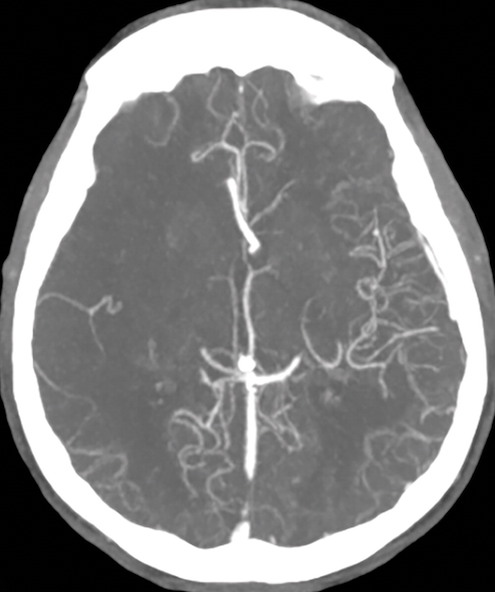

Une équipe américaine a cherché à connaître le degré d’augmentation de l’utilisation de la neuro-imagerie dans un passé récent. Ils ont ainsi identifié, dans une étude publiée dans l'American Journal of Roentgenology (AJR), une croissance importante de 2007 à 2017, la croissance de l'angioscanner cérébral et du cou dépassant les autres modalités. Mais c’est encore la tomodensitométrie crânienne non injectée qui reste le principal examen de neuro-imagerie en urgence.

Le Dr Merdan et ses collègues ont ainsi évalué l'utilisation annuelle de la TDM cérébrale, de l'IRM cérébrale, de l’angioscanner de la tête et du cou, de l'angio-IRM de la tête et du cou, ainsi que les actes d’échographie carotidienne à partir de déclarations anonymisées fournies par le Clinformatics Data Mart (Optum) pour 2007 –2017. Les taux d'utilisation ont été ajustés en utilisant les proportions relatives annuelles des groupes d'âge et classés en fonction des données démographiques des patients, du type de payeur et de l'état du prestataire.

Au cours de cette période, l’étude montre que les taux d'utilisation de la neuroimagerie aux urgences pour 1 000 visites aux urgences, ajustés en fonction de l'âge, ont augmenté de 72 % au total. Plus précisément, l'utilisation de la TDM cérébrale et de la TDM de la tête et du cou a continuellement augmenté de 48 % et de 1 011 % chez les personnes âgées de 65 ans ou plus, dépassant de loin celle des autres modalités de neuro-imagerie.

"La pertinence de cette croissance doit être surveillée à mesure que les indications de l’angioscanner se développent et que davantage de découvertes fortuites sont mises à jour", avertissent les auteurs de cet article.